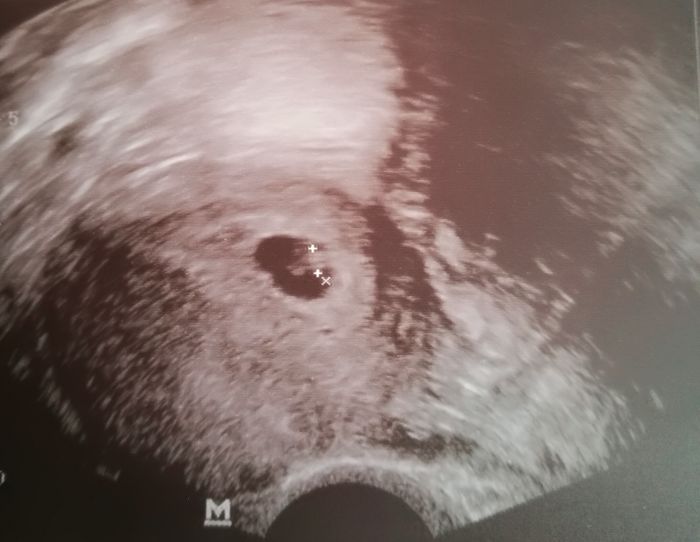

Tak hlasim, ze jsem potvrzena tehule.

Vse je v poradku a od pulky brezna zacnu chodit na ranni. Termin mam konec rijna.

Eriko moc moc gratuluju.nadherna fotka.taky bych chtěla takovou mit

Eriko velká gratulace. Snad i já budu mít ještě takovou fazolku..